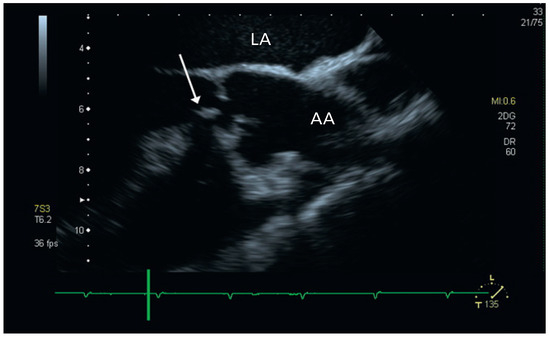

Aortic Valve Rupture Due to a Motorcycle Accident

by Daniela Vocke, Igal Moarof, Peter Matt and Pablo Anabitarte

Cardiovasc. Med. 2011, 14(6), 192; https://doi.org/10.4414/cvm.2011.01597 - 29 Jun 2011

A 62-year-old male patient was admitted as a result of a motorcycle accident [...] Full article